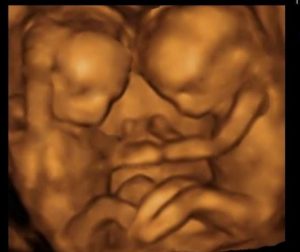

4D Ultra Scan & High Tech Lab

MRS Hospital has well equipped 3D/4D Ultrasonographic scan, 24 hours high risk delivery center, operation theatre, Laparoscopic and Hysteroscopic surgery instruments, infertility department with andrology department, semen bank and embryo storing fecility,Automatic analysers in laboratory, Level 2 New born intensive care equipments to treat low birth weight babies and high risk babies . Our hospital is equipped with latest medical equipments and tools that provide highly effective care to patients.